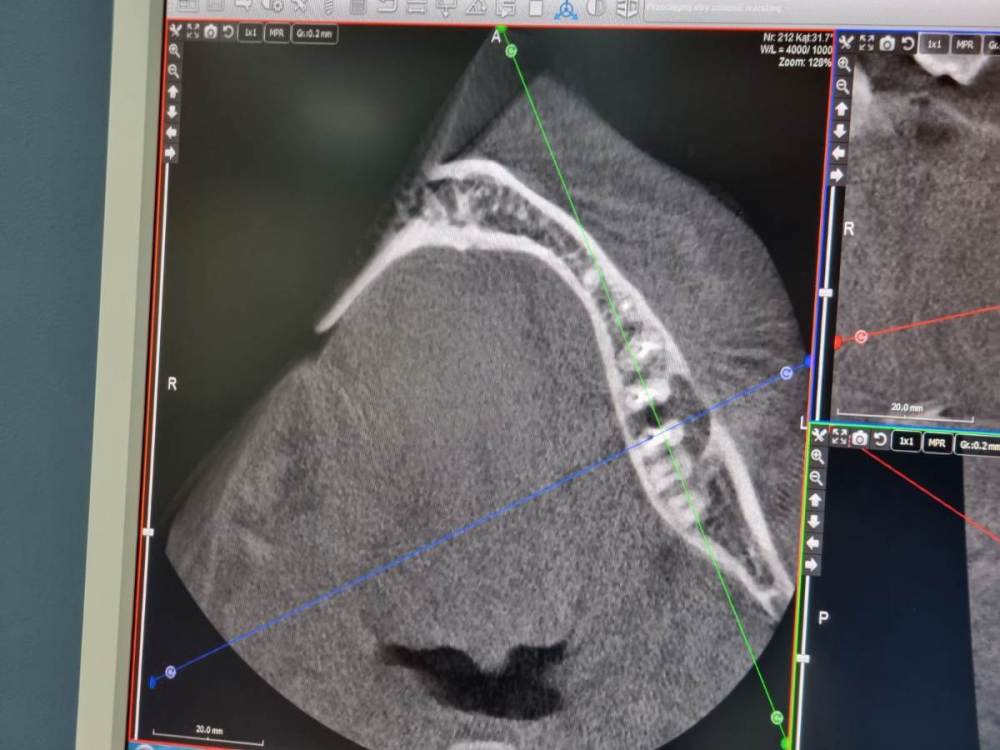

IvanK Опубликовано 21 апреля, 2023 Поделиться Опубликовано 21 апреля, 2023 Здравствуйте, год - это уже срок, не очень актуально, но, исходя из этого снимка, я бы рекомендовал: проверить контактный пункт 15-16, состояние пломб 11,12, на 25 возможно кариес под коронкой 15, 26, 37 оценить по дкт корни, далее протезирование 36 кариес под коронкой оценка контактных пунктов 45-46-47 1 Ссылка на комментарий

Chelovek2012 Опубликовано 15 мая, 2023 Автор Поделиться Опубликовано 15 мая, 2023 (изменено) Был сегодня у врача. 6 Верхний зуб пока запломбировал и не стал ставить имплант. Почему-то. Наверное, увидел более серьезную проблему. НО! Он сказал, что нижний 8 зуб мудрости нужно удалить. Так же 7 зуб говорит что огромная проблема. Говорит, что нужно принимать решение про удаление 8 и нижней 7ки. Два зуба. Потом 4 месяца на то, чтобы там все раросло и еще 4 месяца за работы по импланту 8 месяцев на лечение. Я не представляю, как без 7 зуба столько проходить. Уверенность в себе будет нарушена так на долго Ну и эстетика Год+ назад этого не было. Изменено 15 мая, 2023 пользователем Chelovek2012 Ссылка на комментарий

Chelovek2012 Опубликовано 15 мая, 2023 Автор Поделиться Опубликовано 15 мая, 2023 (изменено) Уже читал про имплантацию.. Возможна ли тут одномоментная имплантация 7 нижнего зуба? Или там воспалительный процесс и это нереально? Как долго можно откладывать имплантацию? Можно ли вылечить воспаление в этом зубе, чтобы его сохранить? Изменено 16 мая, 2023 пользователем Chelovek2012 Ссылка на комментарий